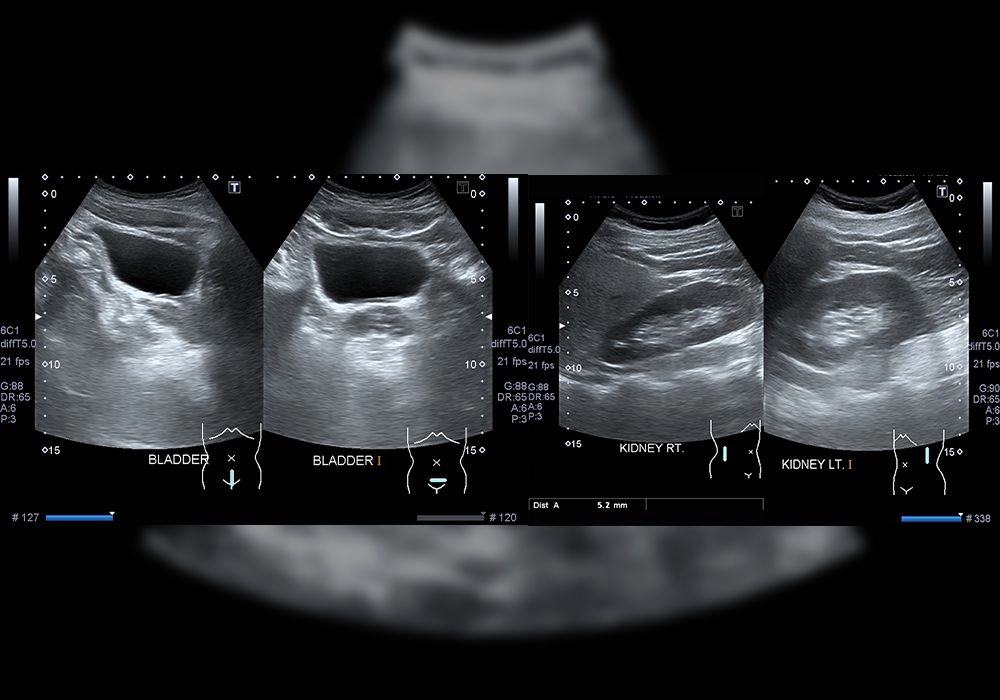

Ultrasound KUB (Kidneys, Ureters, Bladder)

Ultrasound Kidneys, Ureters, Bladder (KUB) is a non-invasive imaging modality focused on assessing the urinary system within the abdomen. Utilizing high-frequency sound waves, a KUB ultrasound examines the kidneys, ureters, and bladder, aiding in the diagnosis of a variety of urinary tract disorders. During the procedure, a handheld transducer is moved across the abdominal surface, capturing detailed images of the organs and their surrounding structures. KUB ultrasound is commonly used to detect conditions such as kidney stones, urinary tract infections, congenital abnormalities, and tumors. It offers the advantage of real-time imaging without the need for ionizing radiation, making it a safe and effective diagnostic tool for evaluating urinary tract health.